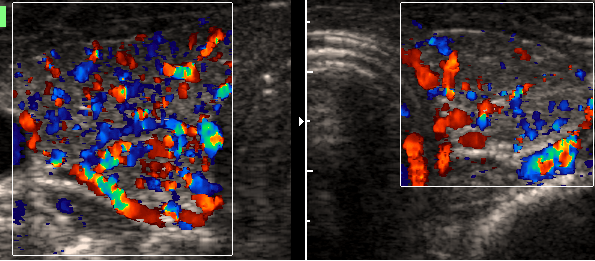

Charakteristik:

|

kleine

Schilddrüse, echoarm

Farbduplex

verminderte

Durchblutung

Diagnose:

Hashimoto

- Thyreoiditis